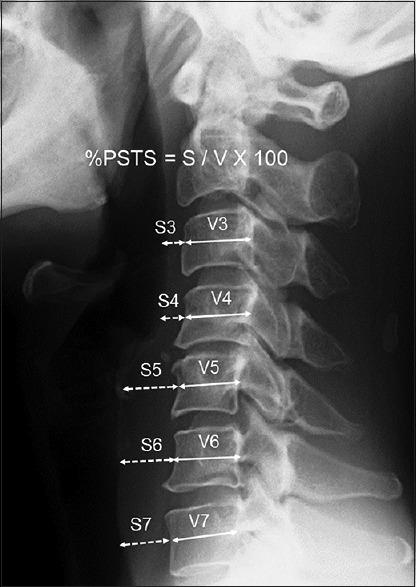

MATERIALS AND METHODS

This study included 152 consecutive patients who underwent 1- or 2-level ACDF using a rectangular titanium stand-alone cage in our institutes. Surgery-related dysphagia early after surgery was analyzed based on hospital charts. Radiological evaluation of prevertebral soft tissue swelling (PSTS) was performed by comparing plain lateral radiographs of the cervical spine before surgery with those after surgery. The percentage of PSTS (%PSTS) was defined by retropharyngeal soft tissue diameter divided by vertebral diameter. Positive %PSTS was determined when %PSTS exceeded its mean + 2 standard deviations.